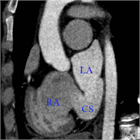

心室中隔欠損症(Ventricular Septal Defect, VSD)

1. 成人循環器内科医が診るVSDのほとんどは小欠損孔のrestrictive VSDとなる。なかにはsmall-moderate size(小~中欠損孔)restrictive VSDで小児期には血行動態的に影響がなかったが、成人期に心室コンプライアンス低下や体血管抵抗の上昇により左→右シャントが増加して左室拡大をきたすことがある。